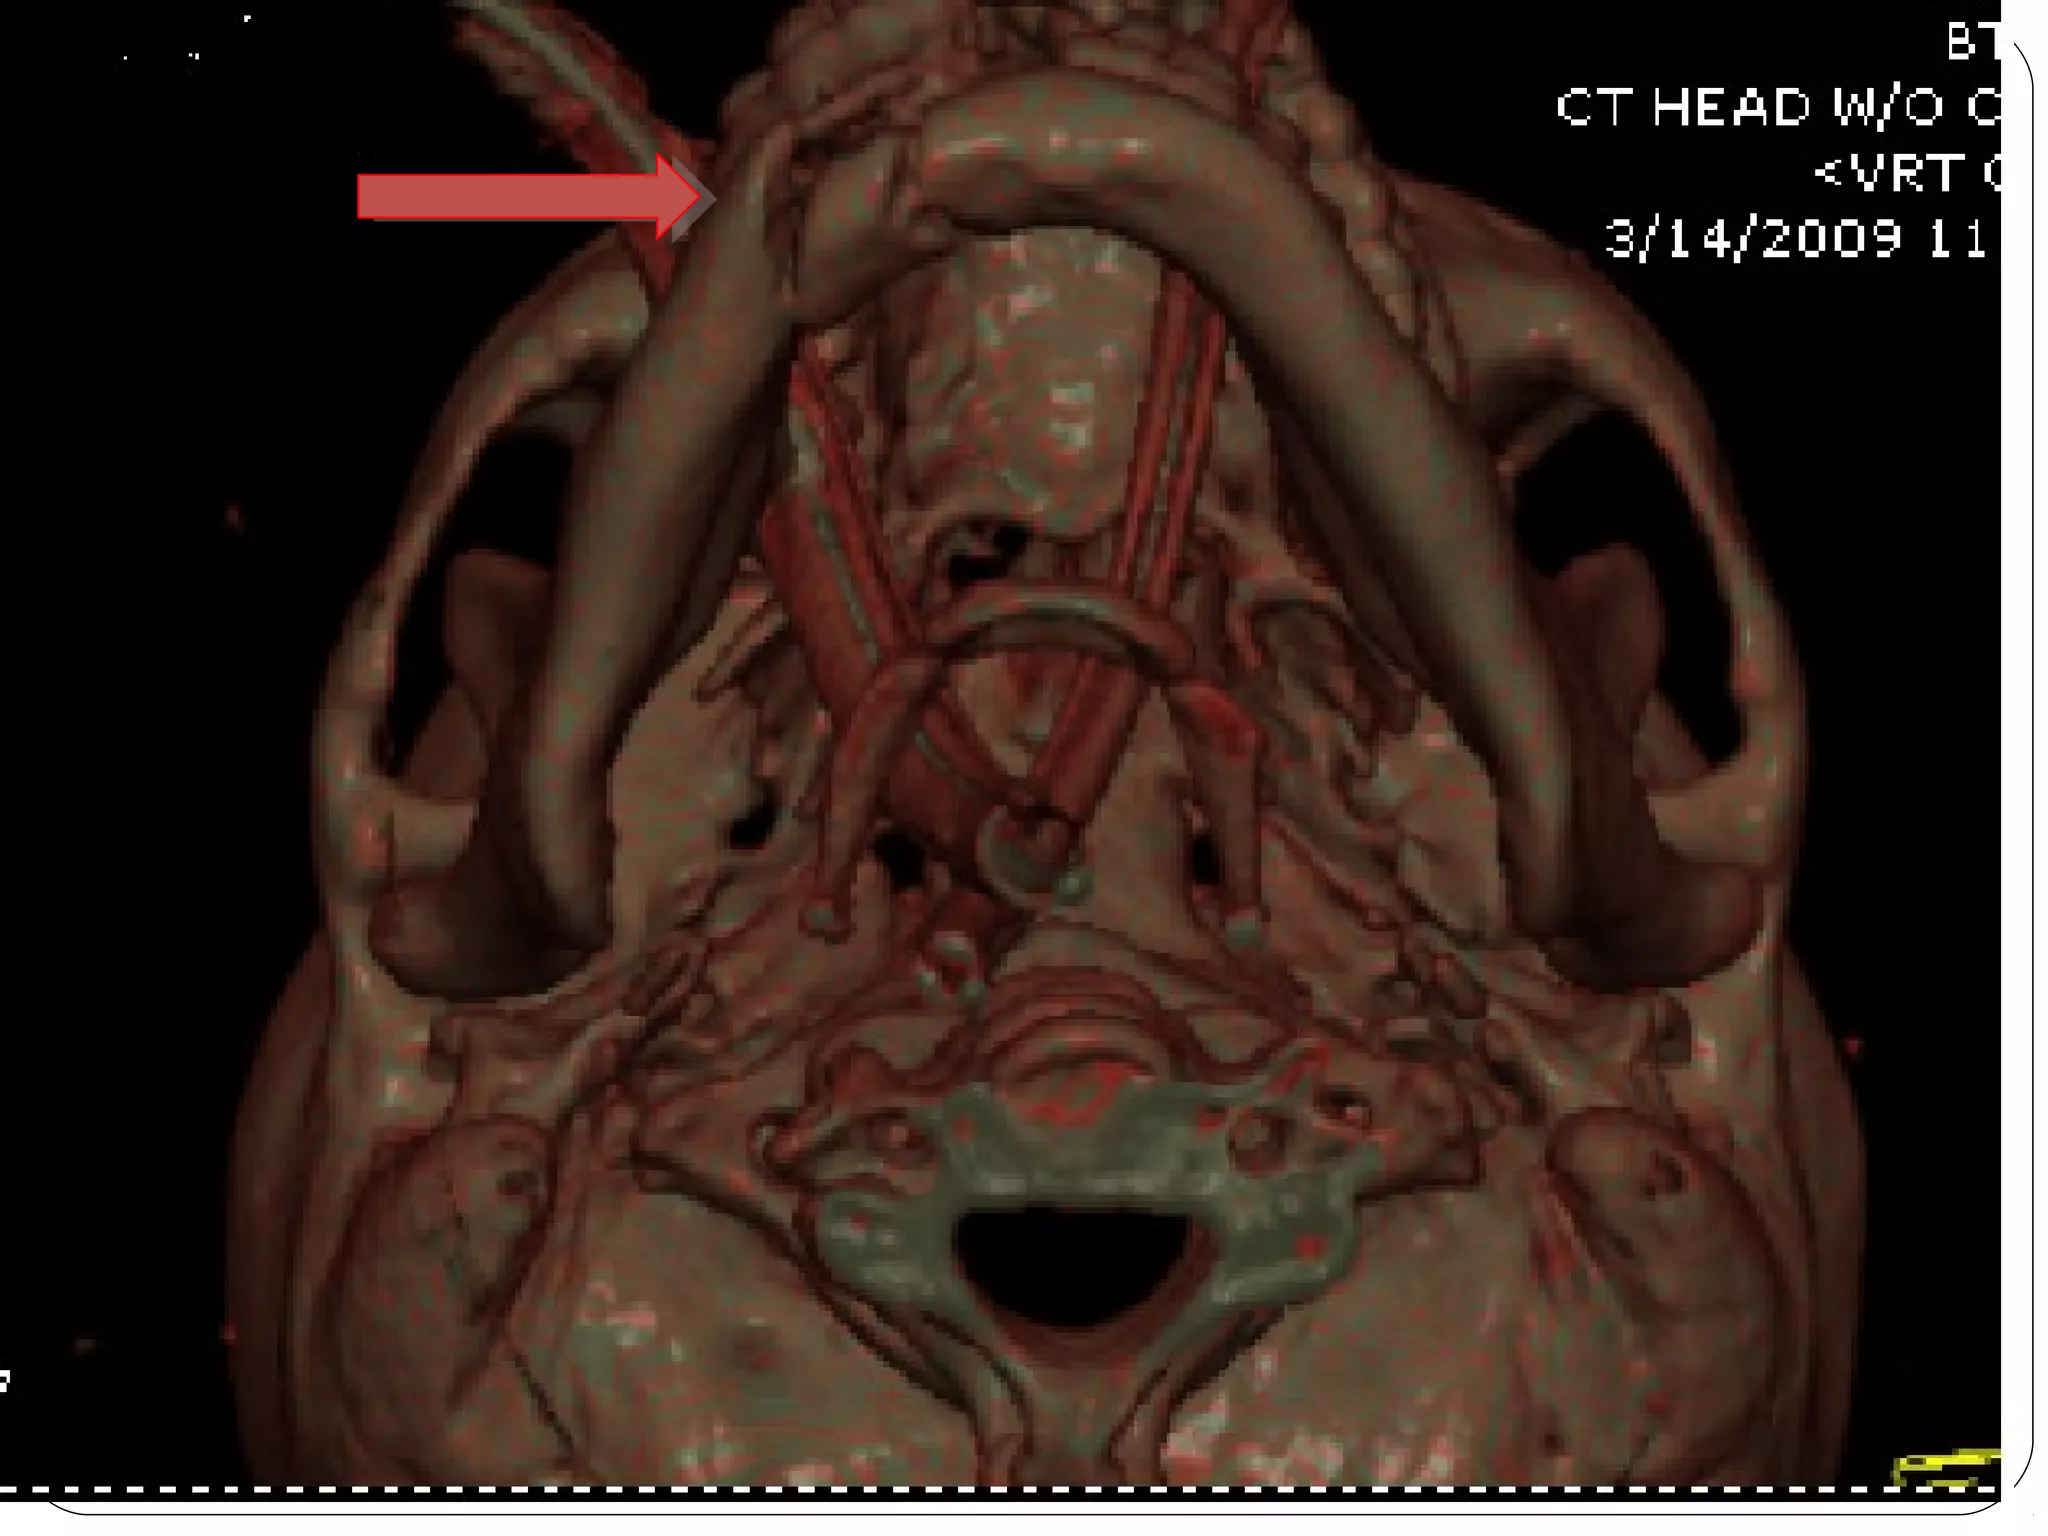

Computed Tomography (CT)

1. Also called CAT scanning or “CT”

2. X-Ray beam moves 360 around the patient

3. Consecutive x-ray “slices” around the patient

4. Computer can recreate 3D image of the body or

Image “slices” reconstructed by computation

5. Best for evaluating bone and soft tissue tumors,

fractures, intra-articular abnormalities, and

bone mineral analysis

Computed Tomography (CT) 1.Also called CAT scanning or “CT” 2. X-Ray beam moves 360 around the patient 3. Consecutive x-ray “slices” around the patient 4. Computer can recreate 3D image of the body or Image “slices” reconstructed by computation 5. Best for evaluating bone and soft tissue tumors, fractures, intra-articular abnormalities, and bone mineral analysis